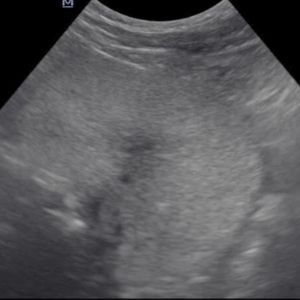

8.Cáncer esplenico (de bazo)

- El cáncer del bazo también puede ser primario o secundario

- Primario más común: Hemangiosarcoma.

- Otros tipos menos frecuentes: linfoma, fibrosarcoma, leiomiosarcoma, histiocitoma maligno, etc.

- En muchos casos, los tumores esplénicos se diagnostican solo cuando se rompen y provocan hemorragia abdominal (hemoperitoneo).

- Ecografías: permiten visualizar tejidos blandos como hígado, bazo, vejiga y próstata.